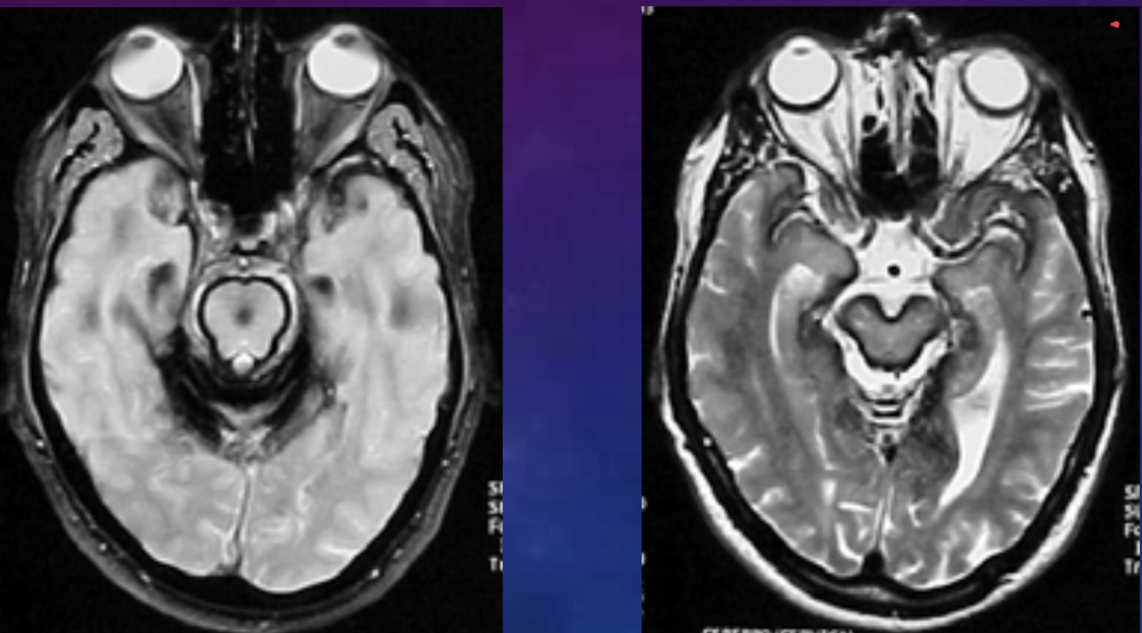

SUPERFICIAL SIDEROSIS - what is it?

SIDEROSIS

(symptoms: vertigo, tinnitus)